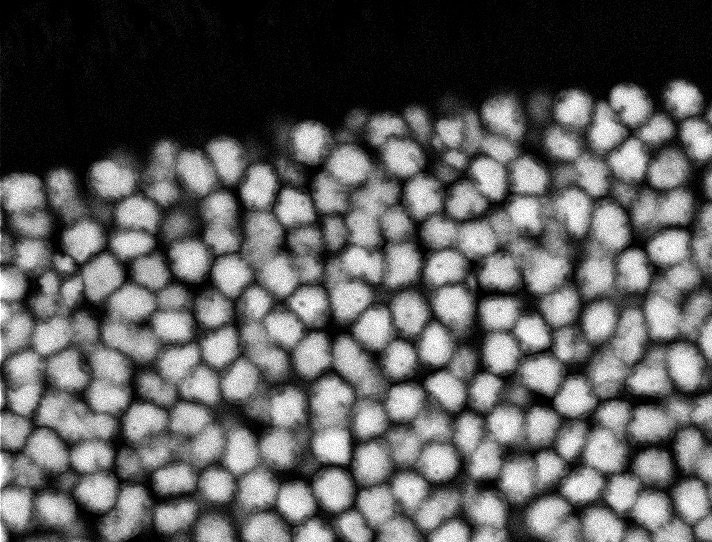

Nuclei